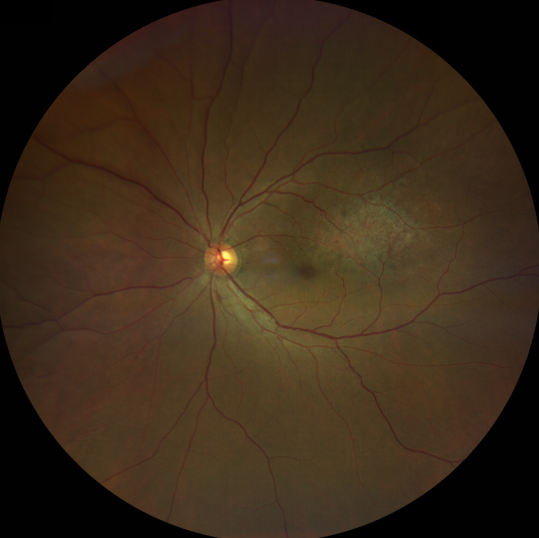

脈絡(luò)膜黑色素瘤是成年人常見的眼內(nèi)惡性腫瘤,其患病率在我國居眼內(nèi)惡性腫瘤的第二位,僅次于視網(wǎng)膜母細(xì)胞瘤。其惡性程度高,不僅可致患者喪失視力,而且嚴(yán)重威脅患者生命,即使在沒有明確轉(zhuǎn)移前摘除患眼眼球,其5年死亡率也有17%-53%。

脈絡(luò)膜黑色素瘤是葡萄膜惡性腫瘤中較多的一種。葡萄膜腫瘤主要發(fā)生于脈絡(luò)膜、睫狀體和虹膜。其中,脈絡(luò)膜腫瘤占80%,睫狀體腫瘤占12%,虹膜腫瘤占8%。惡性程度高的腫瘤主要發(fā)生于脈絡(luò)膜。發(fā)生于睫狀體的腫瘤惡性程度偏低,發(fā)生于虹膜的腫瘤多數(shù)為良性。脈絡(luò)膜黑色素瘤的特點是惡性程度高、易侵襲轉(zhuǎn)移、預(yù)后極差,嚴(yán)重威脅患者的視力和生命。其發(fā)病率有種族差異性,以高加索及白種人居多,黑人發(fā)病率低,亞洲人居于中間。

脈絡(luò)膜黑色素瘤患者在發(fā)病早期無眼痛等癥狀,當(dāng)腫瘤較小時較難發(fā)現(xiàn),隨著病程進(jìn)展,腫瘤增大,發(fā)生滲出性視網(wǎng)膜脫離或累及黃斑,視力下降才就診。

脈絡(luò)膜黑色素瘤惡性程度高,50%的患者會發(fā)生轉(zhuǎn)移,轉(zhuǎn)移到肝、肺等遠(yuǎn)處臟器,常見的轉(zhuǎn)移方式是經(jīng)鞏膜導(dǎo)管擴(kuò)散,經(jīng)視神經(jīng)蔓延者罕見。一旦發(fā)生轉(zhuǎn)移,1年生存率只有10%,即絕大多數(shù)病人在半年至1年間會失去生命。因此,早期診斷和選擇合適的治療方式對有效提高局部腫瘤的控制率、降低腫瘤的遠(yuǎn)處轉(zhuǎn)移率、延長患者的生存率具有重要意義。